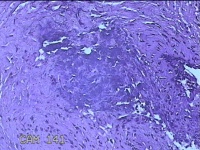

性别

男

年龄

44岁

临床诊断

皮脂腺囊肿

一般病史

右面部起疹12月,不痒。

标本名称

面部肿物

大体所见

灰白粉红色肿物0.5x0.3x0.2cm一个,表面糜烂。